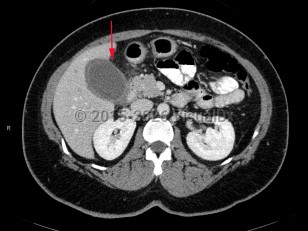

Acute calculous cholecystitis occurs when a gallstone blocks the cystic duct, impairing gallbladder drainage. Temporary obstruction can cause biliary colic. Sustained obstruction can result in gallbladder dilation, wall inflammation, subsequent wall thickening, and pericholecystic fluid accumulation.